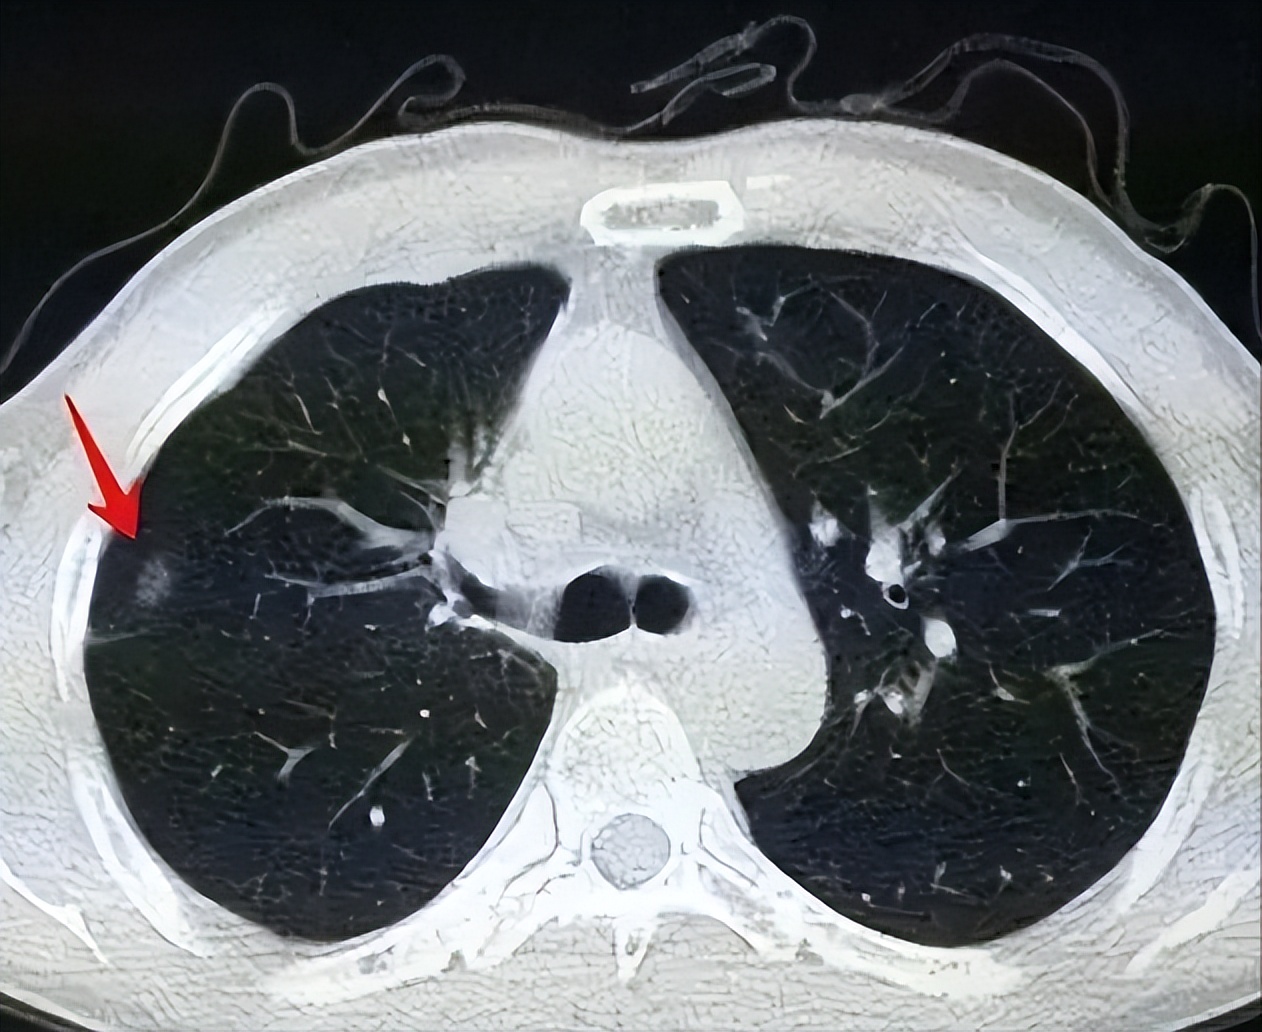

肺结节随着健康查体中CT检查逐渐普及 , 肺结节的检出率也越来越高 , 而肺部结节对胸部的入侵率高达80-90% , 是肺癌患者特有的特征 。 也就是说 , 肺部结节病变是肺癌的其中一个诱因 。

肺结节是指肺内直径≤3cm的类圆形或不规则形病灶 。

1.实性结节

完全是一个高密度的影子 , 在CT下呈现白色的 。 实性结节 , 表面光滑小而圆的 , 多属于良性 。

但如果是部分实性结节 , 其恶性概率相对较高 , 易形成肺腺癌 , 通常由小结节引起 。

2.磨玻璃结节

纯粹的磨玻璃结节 , 体积小于1cm , 边界较清楚 , 多属良性 。 但磨玻璃结节恶变 , 易形成肺鳞癌 , 且高发于男性 。

【ct检查|肺结节到底切不切?一篇文章全说清楚了】3.混合结节

部分毛玻璃 , 部分实变的结节 , 恶性率在60%以上 。